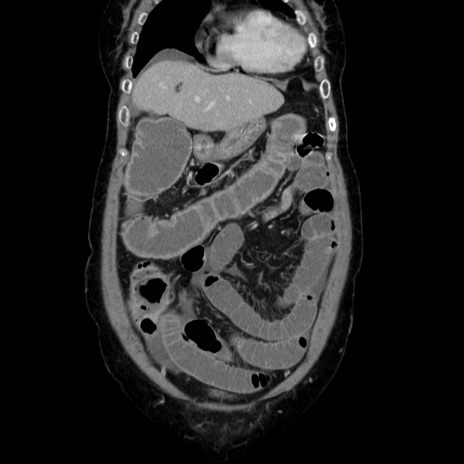

症例5(冠状断像)

【症例】70歳代女性

【主訴】お腹が張る

【現病歴】1週間くらい前から腹部膨満の自覚あり。昨日夜から増悪したため、本日救急外来受診。

【身体所見】意識清明、BT 36.5℃、BP 165/106mmHg、HR 80bpm、SpO2 98%、腹部:膨満、軟、自発痛・圧痛なし、触診にて不快感あり、腸蠕動音:減弱

【データ】WBC 12600、CRP 1.04